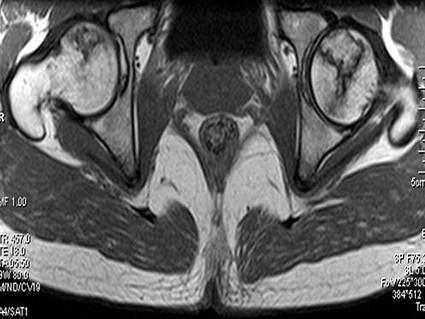

问题 患者,男,24岁,曾有外伤史,两侧髋部疼痛不适数月,请结合所提供的图像,选择最佳答案 ( )

选项 A、化脓性骨关节炎 B、类风湿关节炎两侧 C、髋关节退行性变 D、未见异常 E、股骨头无菌性坏死

答案 E